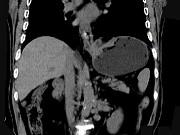

问题 男,75岁,吞咽有梗阻感,消瘦、乏力、中上腹痛,影像检查如图,最可能的诊断是()

选项 A.食道癌 B.胃窦癌 C.贲门癌 D.慢性胃炎 E.胃淋巴瘤

答案 C